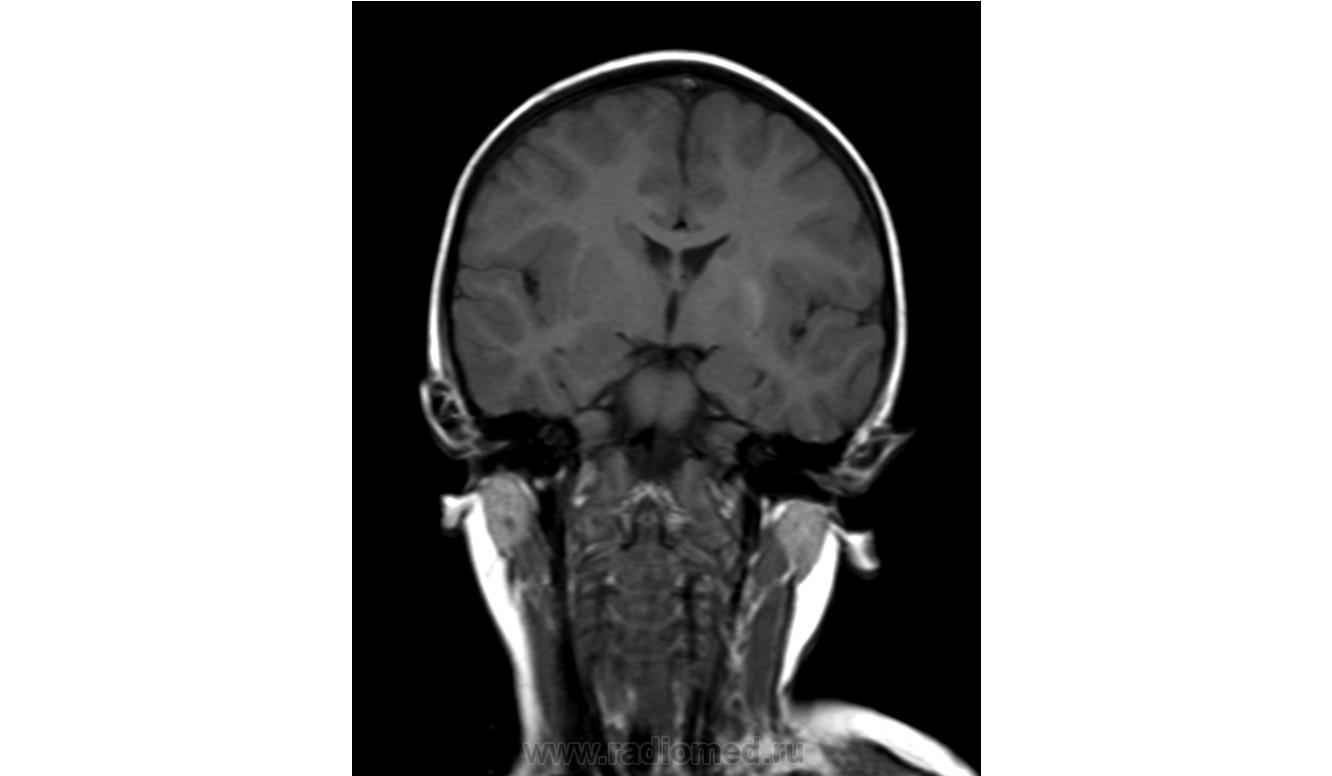

Помогите пожалуйста при постановке диагноза

Ребенок 2 года, заболели в середине декабре, гемипорез, к сожелению не могу ни как с контрасном исследованеим здесь загрузить но накапление контрасного вещества нет, спосибо за помочь!!!!!!!

Предположу гипоксически-ишемические изменения с диапедезным кровоизлиянием. Но они чаще двусторонние.